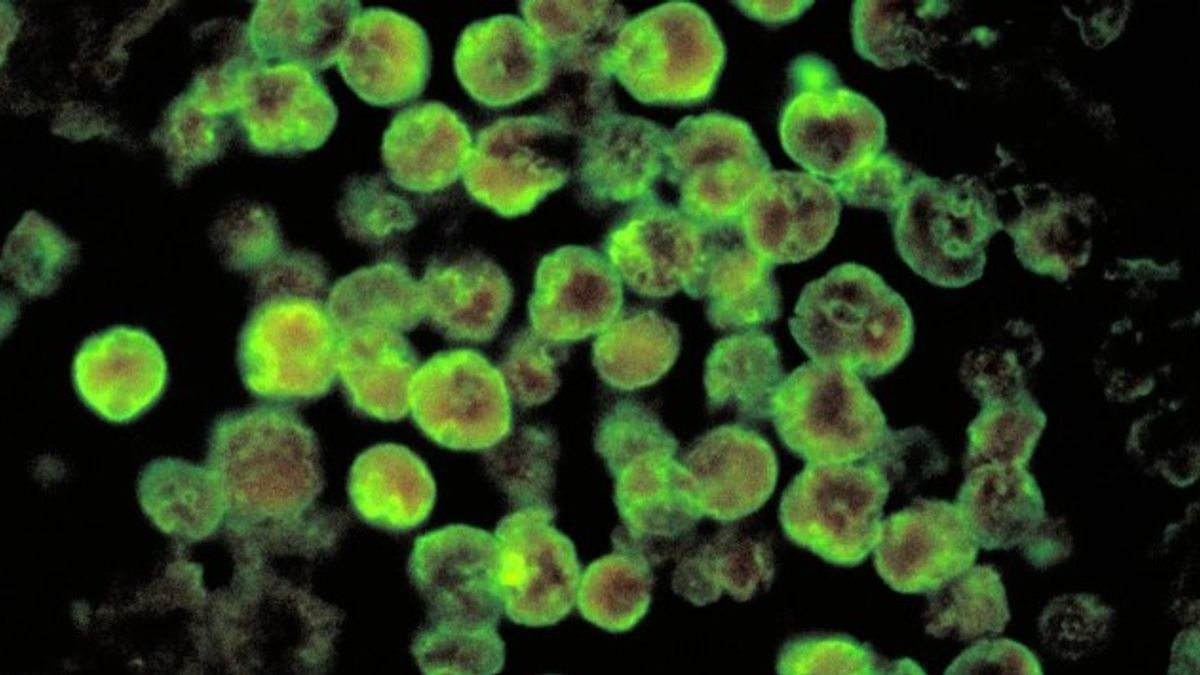

Elsápadtak az orvosok: megállíthatatlan a láthatatlan gyilkos, agyevő amőba szedi sorra áldozatait

A láthatatlan gyilkos egyre több embert fertőz meg.